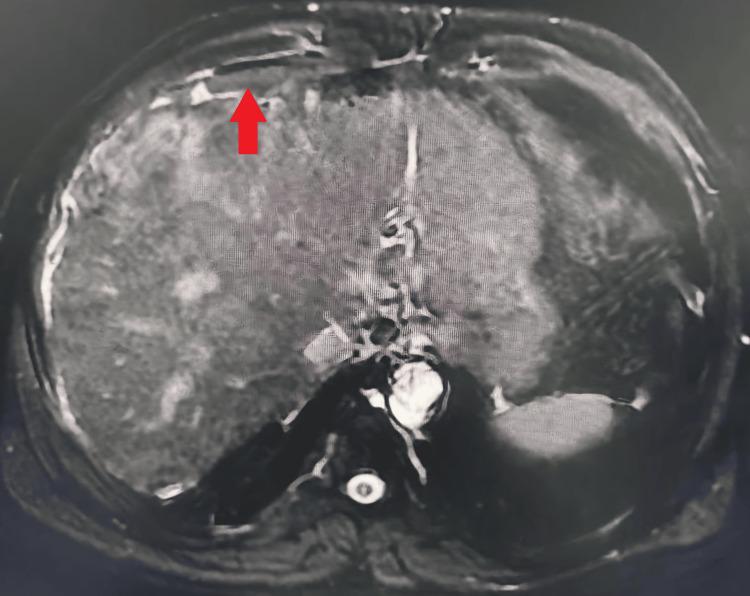

A contracted or "vanishing" gallbladder is a condition characterized by severe atrophy or fibrosis of the gallbladder, often resulting from chronic inflammation, recurrent cholecystitis, gallstone disease, or metabolic disorders such as diabetes and chronic alcohol use. The etiopathogenesis involves progressive fibrosis due to persistent biliary obstruction, chronic infection, or impaired blood flow, particularly in patients with liver cirrhosis. While the exact incidence remains unclear, it is more prevalent in individuals with long-standing hepatobiliary diseases or metabolic syndromes. Common symptoms include severe right upper quadrant pain, jaundice, nausea, vomiting, and signs of obstructive jaundice, such as dark urine and pale stools. Diagnostic investigations typically involve ultrasound, contrast-enhanced computed tomography (CECT), magnetic resonance cholangiopancreatography (MRCP), and endoscopic retrograde cholangiopancreatography (ERCP) to assess biliary obstruction, liver pathology, and gallbladder morphology. Treatment requires a multidisciplinary approach, including initial ERCP for biliary decompression, followed by surgical intervention (laparoscopic or open cholecystectomy), with conversion to open surgery often necessary due to dense adhesions and fibrosis. Postoperative care focuses on managing comorbidities, preventing complications, and long-term monitoring of liver health. This case report presents the challenging management of a 34-year-old male with a history of diabetes mellitus, chronic alcohol use, and liver cirrhosis, who presented with severe right upper quadrant pain, jaundice, and ascites. Initial evaluation revealed cholangitis, calculous cholecystitis with choledocholithiasis, and imaging findings consistent with liver cirrhosis. The patient underwent ERCP for biliary stenting and sludge extraction, followed by an attempted laparoscopic cholecystectomy. Intraoperatively, dense adhesions and fibrosis obscured the gallbladder, confirming a contracted or "vanishing" gallbladder, prompting conversion to an open procedure. The case highlights the diagnostic complexities of contracted gallbladders, which often result from chronic inflammation, fibrosis, or metabolic disorders. Preoperative imaging, including ultrasound and MRCP, played a critical role in identifying biliary obstruction and liver pathology. However, intraoperative findings necessitated adaptive surgical decision-making to mitigate risks such as bile duct injury or hemorrhage. The patient's multiple comorbidities further complicated management, emphasizing the need for a multidisciplinary approach involving gastroenterologists, surgeons, and hepatologists. Postoperative recovery was closely monitored for complications, including infection and bile leaks. The patient was discharged with follow-up care focusing on liver health, diabetes management, and alcohol cessation. This report underscores the importance of thorough preoperative assessment, flexibility in surgical technique, and collaborative care in optimizing outcomes for patients with complex gallbladder pathology. Future research should explore long-term outcomes and improved imaging techniques to enhance surgical planning for such challenging cases.

胆囊萎缩或“消失”是一种以胆囊严重萎缩或纤维化为特征的病症,通常由慢性炎症、复发性胆囊炎、胆结石病或代谢紊乱(如糖尿病和长期酗酒)引起。其发病机制涉及由于持续性胆管梗阻、慢性感染或血流受损导致的进行性纤维化,在肝硬化患者中尤为常见。虽然确切发病率尚不清楚,但在患有长期肝胆疾病或代谢综合征的个体中更为普遍。常见症状包括右上腹剧痛、黄疸、恶心、呕吐以及梗阻性黄疸的体征,如尿色深和大便色浅。诊断性检查通常包括超声、增强计算机断层扫描(CECT)、磁共振胆胰管造影(MRCP)和内镜逆行胆胰管造影(ERCP),以评估胆管梗阻、肝脏病理和胆囊形态。治疗需要多学科方法,包括首先进行ERCP以解除胆管梗阻,随后进行手术干预(腹腔镜或开腹胆囊切除术),由于致密粘连和纤维化,通常需要转为开腹手术。术后护理重点在于管理合并症、预防并发症以及对肝脏健康进行长期监测。本病例报告介绍了一名34岁男性患者的具有挑战性的治疗过程,该患者有糖尿病、长期酗酒和肝硬化病史,出现右上腹剧痛、黄疸和腹水。初步评估显示胆管炎、结石性胆囊炎伴胆总管结石,影像学检查结果与肝硬化相符。患者接受了ERCP胆管支架置入和胆泥清除,随后尝试进行腹腔镜胆囊切除术。术中,致密粘连和纤维化使胆囊难以辨认,证实为萎缩或“消失”的胆囊,促使手术转为开腹手术。该病例突出了萎缩性胆囊的诊断复杂性,这通常由慢性炎症、纤维化或代谢紊乱引起。术前影像学检查,包括超声和MRCP,在识别胆管梗阻和肝脏病理方面发挥了关键作用。然而,术中发现需要灵活的手术决策以降低胆管损伤或出血等风险。患者的多种合并症使治疗更加复杂,强调了需要胃肠病学家、外科医生和肝病学家参与的多学科方法。术后密切监测恢复情况以预防并发症,包括感染和胆漏。患者出院时接受以肝脏健康、糖尿病管理和戒酒为重点的随访护理。本报告强调了全面术前评估、手术技术灵活性以及协作护理对于优化复杂胆囊病理患者治疗效果的重要性。未来研究应探索长期预后以及改进成像技术,以加强对此类具有挑战性病例的手术规划。